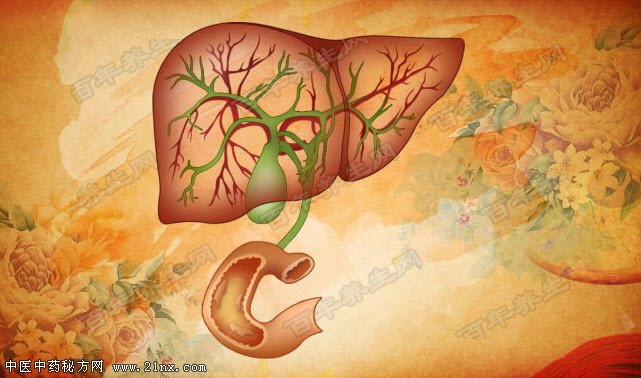

图:胆囊 胆囊疾病的发病率非常高,能达到10%以上,胖人比瘦人多发,且女性比男性多发,尤其是偏胖的女性更多发。 哪些情况是胆囊疾病的高危因素呢?胆囊疾病与高脂饮食密切相关,所以我们不仅要重视吃什么,还要特别注意怎么吃,针对健康人群和已患胆囊疾病的人群,您知道一日三餐中分别都是哪一餐需要特别注意吗?科学面对胆囊疾病,我们还能主动做些什么?